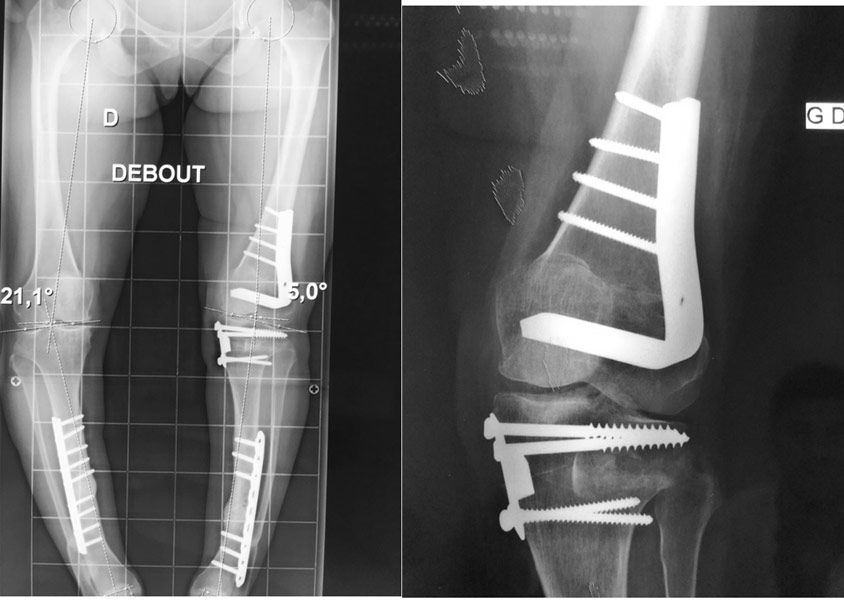

Déformation du genou en valgus (jambes en X), femme jeune (45 ans), ancienne handballeuse aux jeux de Séoul ; le fémur et le tibia sont déformés. Handicap majeur.

On réalise une double ostéotomie de varisation lors de la même opération, fémorale et tibiale, fixées avec des agrafes métalliques.